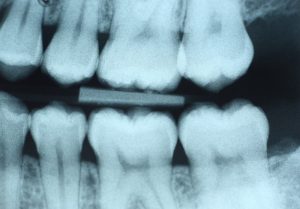

Digital x-rays use 80% to 90% less radiation than traditional film x-rays. That means the radiation exposure is “extremely small,” and that digital dental x-rays “represent a far smaller risk than undetected and untreated dental problems”

(Source: American Academy of Pediatric Dentistry)